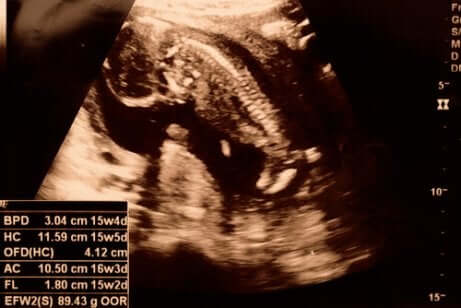

Kun 15. raskausviikko koittaa, raskaus on kestänyt 14 viikosta ja 0 päivästä 14 viikkoon ja 6 päivään. 12 viikkoa vanha sikiö on tässä vaiheessa noin 8 senttimetrin pituinen ja 50 gramman painoinen.

15. raskausviikolla sikiön luuranko ei ole vielä kehittynyt, mutta sen selkäranka ja hermopäätteet ovat jo nähtävissä. Sen kädet ja jalat kasvavat, ja se pystyy jo taivuttamaan niveliään ja liikuttamaan käsiään. Kädet ovat jo lähes saavuttaneet lopullisen paikkansa, mutta jalat ovat edelleen suhteellisen lyhyet. Sikiön pää on edelleen vartaloon nähden suuri, mutta se pysyy jo pystyssä kaulan ja niskan avulla. Sikiö alkaa harjoitella imemistä, ja imemiseen tarvittavien lihasten kehittymisen myötä sen kasvot alkavat saada pyöreät piirteet. Vaikka sikiön silmät pysyvätkin edelleen kiinni, se pystyy jo aistimaan valon.

Sikiön keuhkot kehittyvät edelleen, ja se alkaa hengittää sisään ja ulos pieniä määriä lapsivettä. Tämä on erittäin tärkeää keuhkojen kehittymisen kannalta. Sikiö pystyy myös jo maistamaan erilaisia makuja lapsivedessä. Se alkaa totutella ensimmäisiin makuihin nimenomaan juomalla lapsivettä, jonka makuun äidin syömä ruoka vaikuttaa. Tässä vaiheessa raskautta sikiön sydän pumppaa noin 28 litraa verta joka päivä.